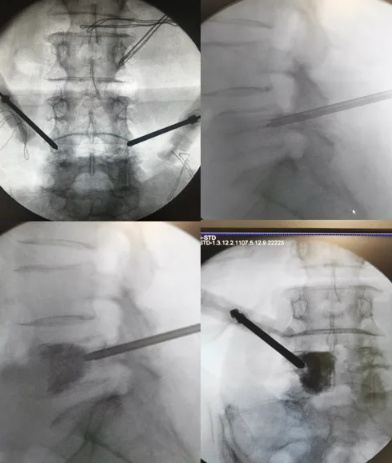

·患者凌某某,女,65岁,因反复腰背部疼痛半年余入院。腰背痛VAS评分6分。

·诊断:1.腰5椎体转移瘤(ESCC,0级);2.直肠癌

首例局麻下智能控温射频消融联合椎体成形术治疗脊柱转移瘤

患者手术全程保持清醒,射频消融过程中无任何不适。术后第一天佩戴腰围起床活动。术后腰背痛VAS评分3分。